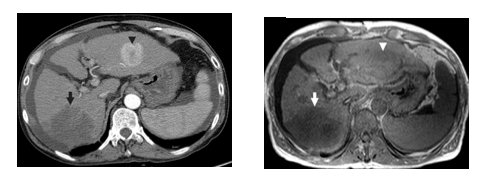

On the one hand, a CT scan (Figure 16, left) creates a cross sectional, 3D image of the body.  The scan gives detailed pictures of the tumour(s) and surrounding tissues and organs, enabling the doctors treating you to gain an accurate picture of the tumour, and its location. On the other hand, MRI (figure 16, right) uses magnetic and radio waves (not X-rays) to show the tumour(s) in great detail and look at the blood supply to the liver.  Also, for both CT and MRI, the patient may be given an injection of a contrast medium during the scan in order to produce a better image [32].

Draft Samper 627449012-image23.png

Figure 16. Medical imaging techniques applied to the abdominal field (axial view): CT (left) and MRI (right) [29]